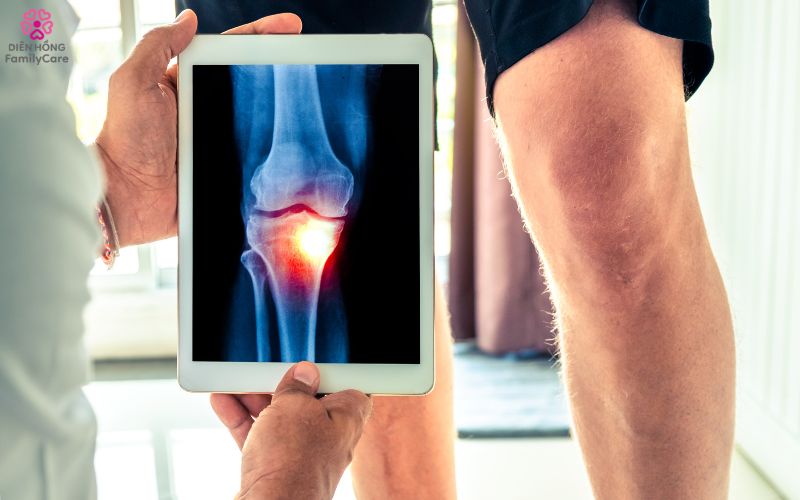

📌 Nếu người cao tuổi có nhiều dấu hiệu trên, nên đi khám sớm để được chẩn đoán bằng X-quang, MRI hoặc siêu âm khớp.